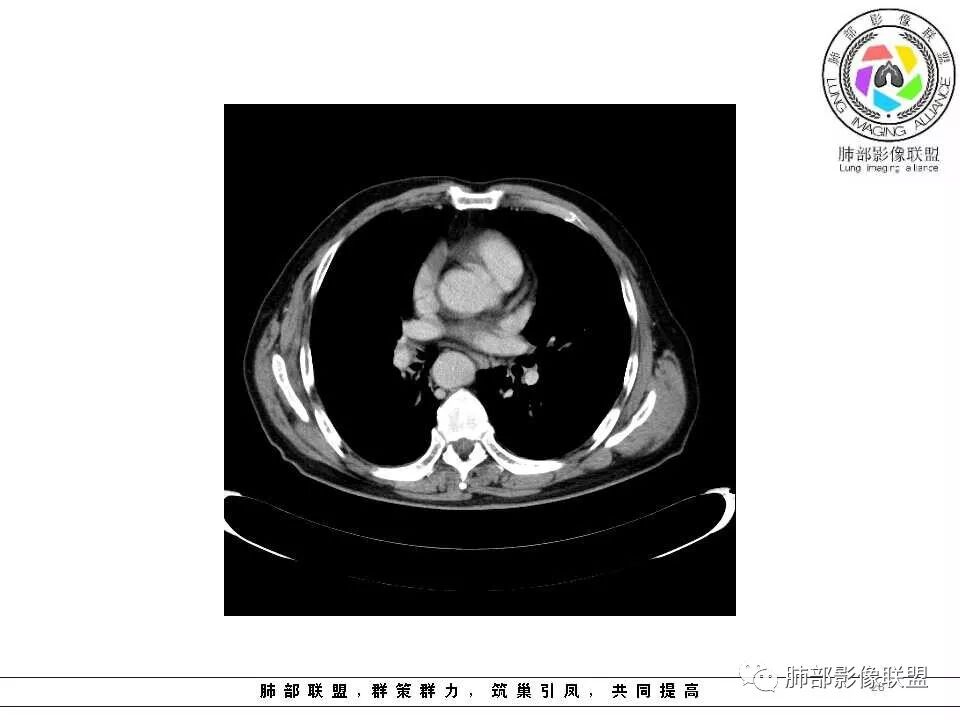

纵隔窗上似乎结节内可见点状高密度影,同时没有明显肿大淋巴结

老年男性,肺气肿基础。约一年时间出现左肺上叶舌段支气管近端结节影,远端斑片样阴影,边缘模糊。考虑近端恶性占位,远端有阻塞性炎症。

老年男性,两肺可见小叶中央型肺气肿,提示应该有抽烟史。2016年片,右肺门支气管稍模糊,考虑慢性感染,纵膈淋巴结稍大。但2017年左肺上叶新发占位,堵塞支气管,引起局部肺不张伴感染,且纵膈淋巴结较2016年变大,患者同时伴有咯血,考虑恶性。鳞癌?类癌?小细胞?

肺气肿背景,2016年左肺上叶上舌段见微结节,2017年5月左肺结节增大,密度均匀,边缘光滑锐利,与邻近血管关系密切,血管贴壁走行,外侧见尖状突起,下舌段片状影,沿着支气管走行,内有粘液栓,考虑鳞癌,鉴别小细胞肺癌。

肺气肿背景,2016年左肺上叶上舌段见微结节,一年后左肺结节增大,密度均匀,边缘光滑、膨隆,似见小分叶,下舌段片状影,沿着支气管走行,内,老年患者,咯血1月。考虑恶性病变并阻塞性肺炎,鳞癌?注意鉴别结核。

左肺上叶舌段支气管管壁略增厚 间隔一年 管壁增厚明显 向腔外突出形成结节 管腔闭塞 远端片状及斑片影 纵隔淋巴结增大 肺气肿背景 考虑鳞癌伴阻塞性炎症可能